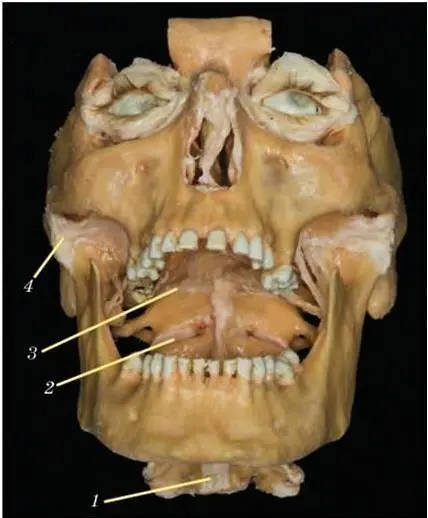

Рис. 44. Соединения затылочной кости, I шейного позвонка (атланта) и II шейного позвонка (осевого).Вид через раскрытый рот. Натуральный анатомический препарат. Полимерное бальзамирование:

1 – передняя продольная связка; 2 – атланто-осевой сустав; 3 – капсула атлантозатылочного сустава; 4 – капсула височнонижнечелюстного сустава